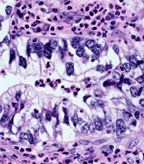

Clear cell carcinoma of the lung